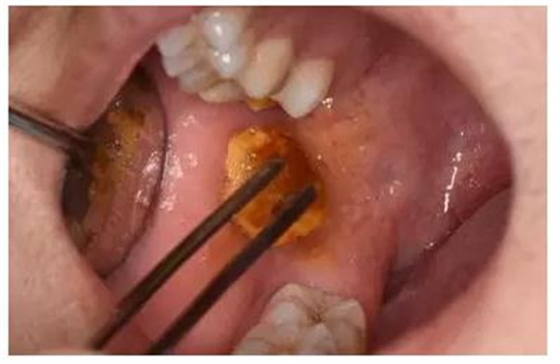

圖4.局部注射區(qū)粘膜碘伏消毒